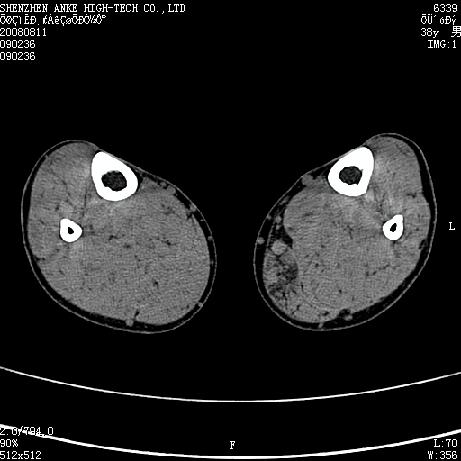

标题: CT15117:M38Y,小腿平扫 [打印本页]

标题: CT15117:M38Y,小腿平扫

患者,男,38岁,右小腿疼痛性包块1月,查体:右小腿可扪及约5x4cm大小包块,压痛.

左小腿内侧软组织病变,性质待定(血管瘤?);建议行mri检查。